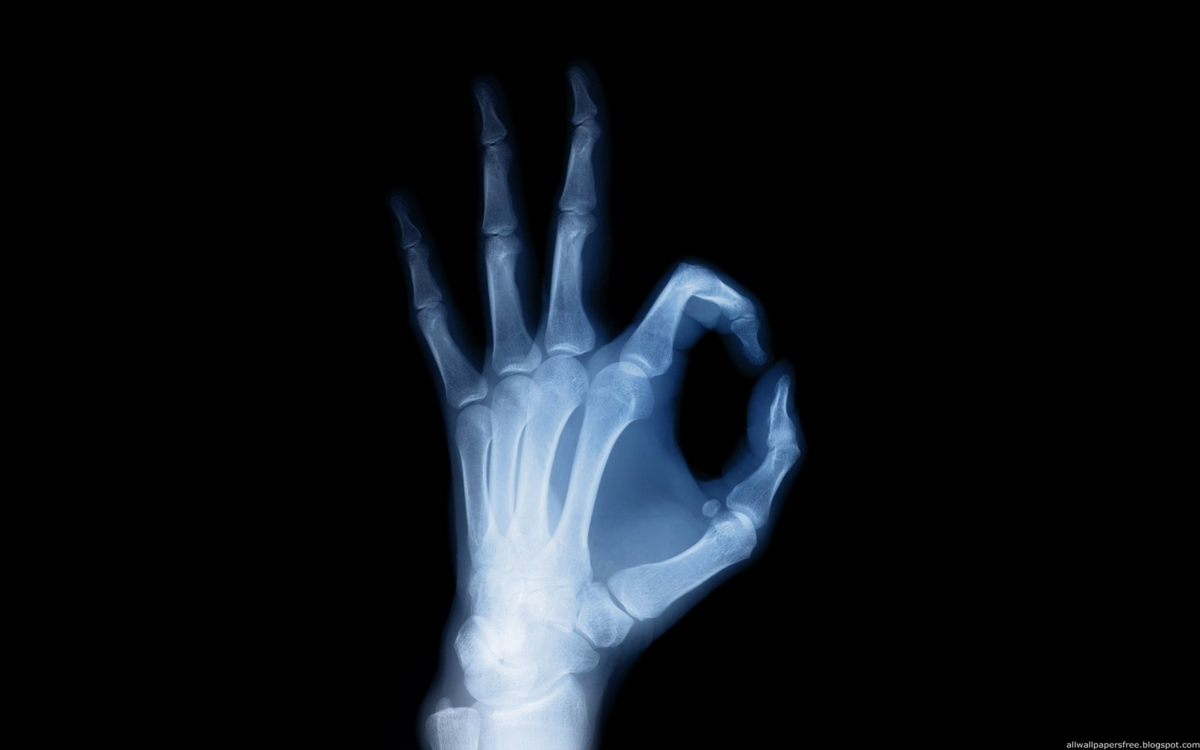

2 место: Рентгеновские лучи

кисть под рентгеном

Врачи прошлого даже не догадывались, что когда-либо смогут "заглянуть внутрь" человека без хирургического вмешательства. Знаменитый немецкий ученый Вильгельм Конрад Рентген случайно открыл новое явление, когда уходил из своего кабинета. Уже собираясь уходить, он затушил лампу и увидел слегка зеленоватое свечение, возникающее при работе катодно-лучевой трубки. Если бы не его открытие, которое он позже назвал Икс-лучами, то сегодняшняя медицина была бы совсем иная.